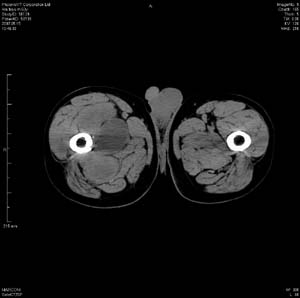

男 63岁 右大腿无痛性肿块11年,x片右大腿软组织肿块影,余无明显异常.ct值-13__239hu

右大腿股内侧股与收肌间隙间多发囊实性占位,界清.内示斑点状钙化.局部骨质无异常.肌肉推压移位表现.

考虑肌间隙病变.可有1,神经来源肿瘤.2,血管来源病变.3,淋巴来源肿瘤.4,脂肪来源肿瘤.5,滑膜来源肿瘤.结合病史只能考虑良性占位.建议增强或mri进一步分析.

同意,病史较长,病变周围分界清晰,考虑良性病变。病灶内有多发斑点状钙化,沿肌间隙生长,血管瘤或淋巴管瘤首先考虑。